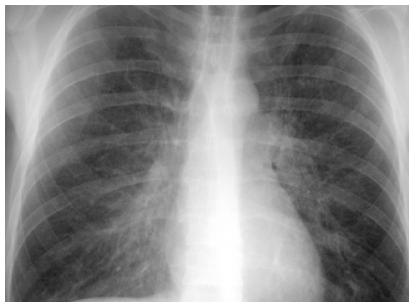

图7 感染性间质性肺炎胸部正位片可见双侧弥漫性间质性改变,痰培养

间质性肺炎x线

间质性肺炎胸片

间质性肺炎x线图片